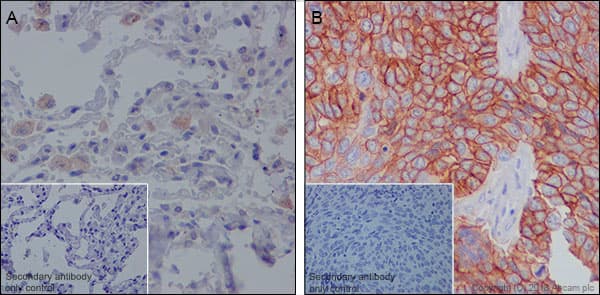

Anti-MRP1 antibody [EPR21062](ab233383)

Rabbit Recombinant Monoclonal MRP1 antibody. Suitable for WB, ICC/IF, IHC-P and reacts with Human samples. Cited in 22 publications.

Applications ICC/IF, IHC-P, WB

Species Reactivity Human